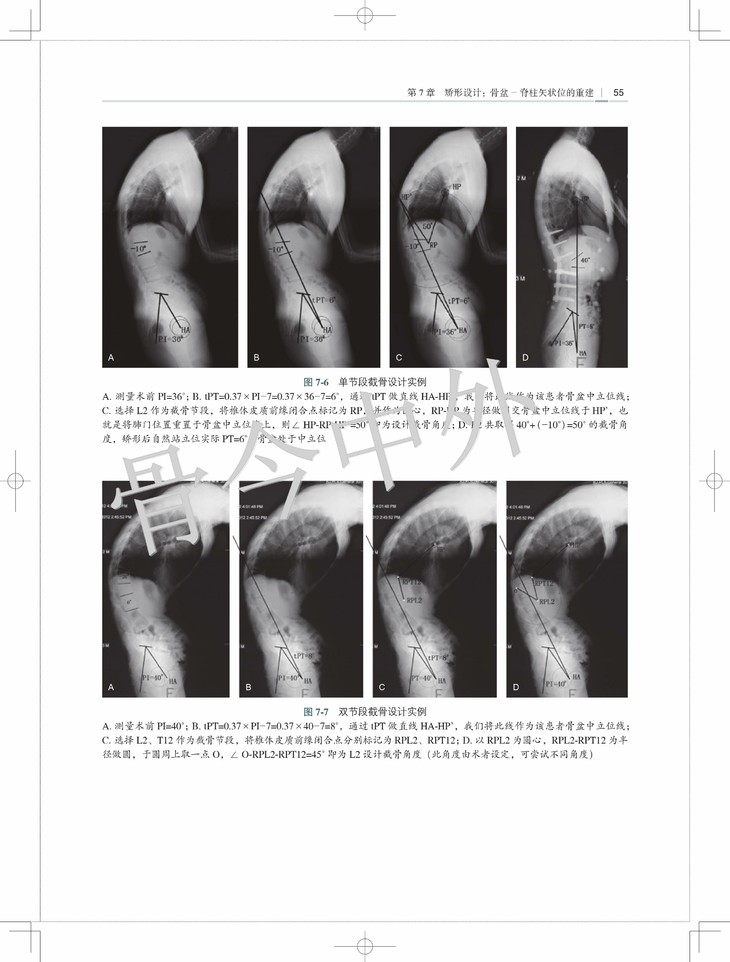

第7 章· 矫形设计:骨盆- 脊柱矢状位的重建 50

五、矢状面平衡的截骨矫形设计/ 54

六、骨盆中立位的个性化设计/ 54